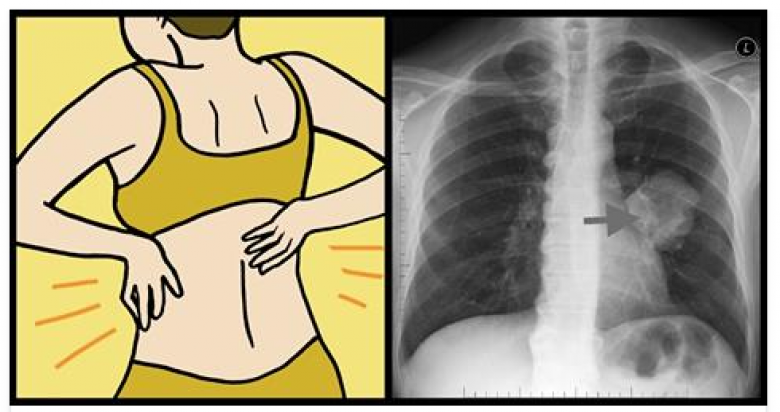

Թոքերի քաղցկեղի 8 նշան, որ յուրաքանչյուր կին պետք է իմանա

Առողջության հետ կատակ չեն անում: Լավագույնը, որ մենք կարող ենք անել՝ մշտապես ուշադիր լինելն է մեզ և մեր մարմնի անգամ չնչին փոփոխություններին: Իհարկե, միայն բժիշկը կարող է ճշգրիտ ախտորոշում անել, սակայն ոչ ոք մեզնից լավ չգիտի մեր մարմինը: Ավելին, կանացի մարմինը կարող է ցուցաբերել այլ աշտանիշներ, քան տղամարդկայինը: Համաձայն վիճակագրության՝ թոքերի քաղցկեղից մահանում են ավելի շատ կանայք, քան տղամարդիկ:

BlogNews-ը ձեզ է ներկայացնում թոքերի քաղցկեղի 8 նշան, որ յուրաքանչյուր կին պետք է իմանա:

4. Մեջքի և ուսերի ցավեր

Հավանաբար դուք չեք կապում մեջքի ցավերը թոքերի հետ, սակայն կանանց մոտ մեջքի և ուսերի հատվածում սուր ցավերը կարող են ուղիղ կապ ունենալ շնչառական համակարգի խնդիրների հետ: Պատճառն այն է, որ կանայք ավելի հակված են ունենալ թոքերի քաղցկեղի ադենակարցինոմա տարատեսակը: Քաղցկեղի այս տարատեսակի ուզուցքներն առաջանում են թոքերի արտաքին շերտերում և կարող են ճնշում գործադրել կողոսկրերի և ողնաշարի վրա:

8. Ցավեր կրծքավանդակում

Ադենակարցինոման ունենում է փոքր ինչ այլ ախտանշաններ, քան թոքերի քաղցկեղի այլ տարատեսակները: Այն կարող է առաջացնել ցավեր կրծքավանդակում, ինչպես նաև մեջքի հատվածում: Այնպես որ, եթե դուք ունեք շարունակական ցավեր կրծքավանդակի հատվածում շտապեք այցելության գրանցվել բժշկի մոտ: